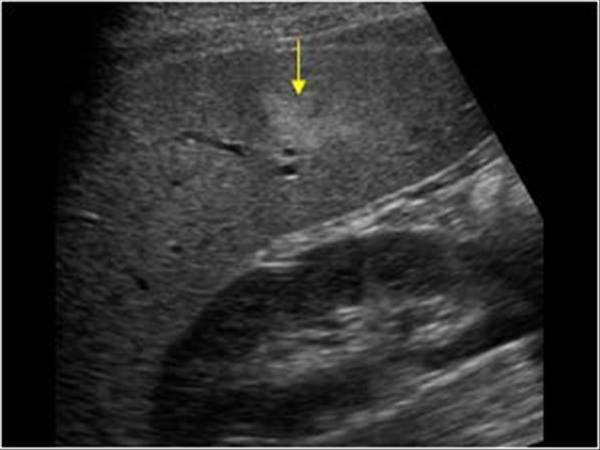

pneumobilia

Air within the biliary tree